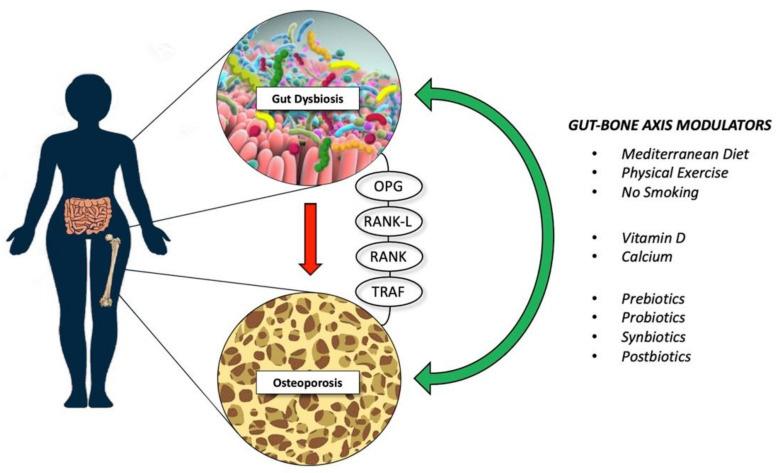

Modulation of gut microbiota by other means such as diet, synbiotics, postbiotics, antibiotics, and fecal microbiota transplantation is another way to influence the gutbone axis and improve bone health.

The Mediterranean diet can have a beneficial ef

fect on reducing the risk of bone fractures due to the high content of fiber, fermented milk products and polyphenols that favorably change the composition of the intestinal microbiome (Figure 2).

FIGURE 2 Gut microbiota modulators Lifestyle intervention and supplementation that might reduce bone loss; these modulators might exert their therapeutic effects through different known biological pathways, such as OPG, RANK, and TRAF. Abbreviations — OPG: osteoprotegerin; RANK-L: receptor activator of nuclear factor-κB ligand; RANK: receptor activator of nuclear factor κB; TRAF: tumor necrosis factor receptorassociated factor. Taken from: deSire A, deSire R, Curci C, Castiglione F, Wahli W. Role of Dietary Supplements and Probiotics in Modulating Microbiota and Bone Health: The GutBone Axis. Cells. 2022Feb21;11(4):743.doi:10.3390/cells11040743.PMID:35203401;PMCID:PMC8870226.